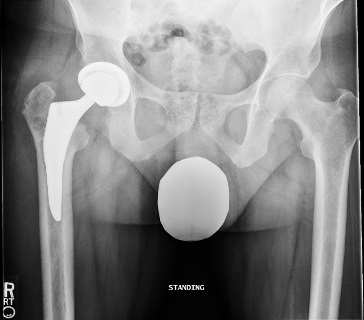

Total hip replacement was the treatment of choice for this case taking into consideration the poor bone stock available after removal of the metalwork and high risk of avascular necrosis which would have compromised the outcome of revision ORIF or a valgus osteotomy. This was the consensus at a multi-disciplinary meeting including the trauma surgeon who performed the initial operations, hip preservation surgeons who specialise in various osteotomies, and arthroplasty surgeons.

Postoperative radiographs were satisfactory: